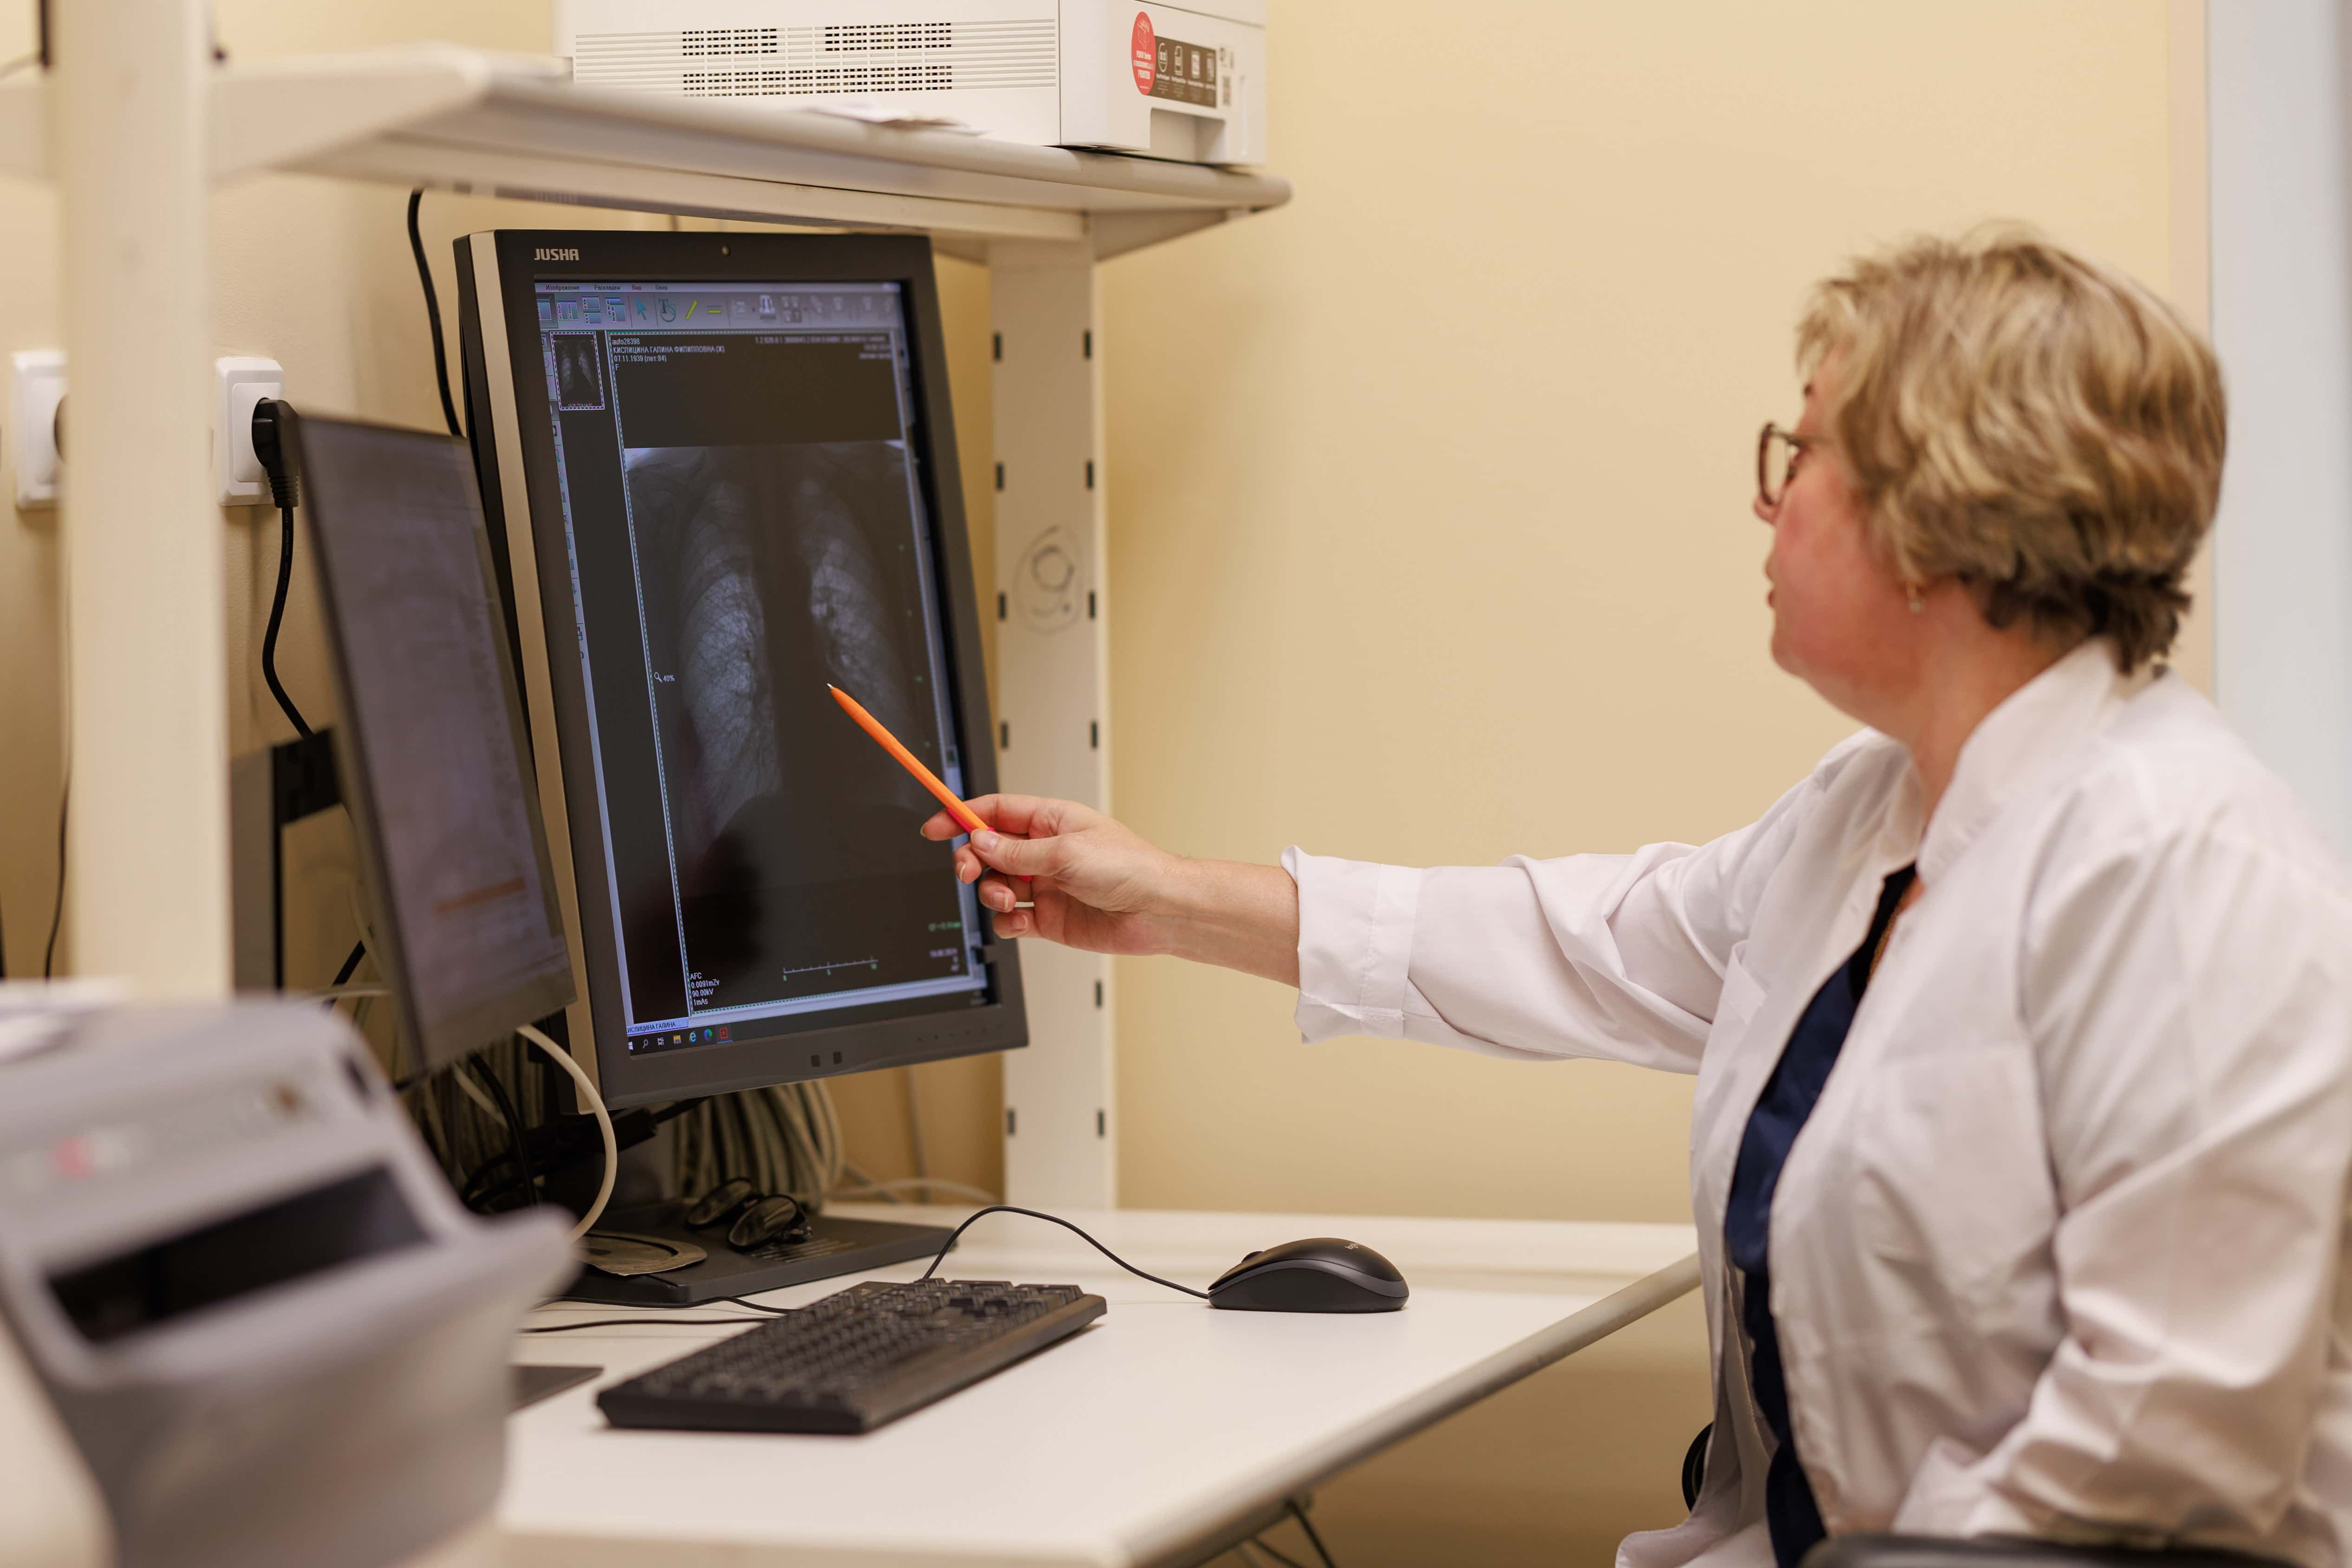

Диагностическую службу взрослой поликлиники Центральной городской клинической больницы №23 усилили обновлённые компьютерный томограф и флюорограф. Теперь для екатеринбуржцев, проживающих на Эльмаше, стали доступнее рентген-диагностические исследования на современном оборудовании для выявления злокачественных новообразований лёгких. Обновление технопарка проводится в рамках федерального проекта «Модернизация первичного звена здравоохранения», входящего в нацпроект «Здравоохранение».

Главным способом борьбы с раковой опухолью является её выявление на максимально ранней стадии. Для этого в рамках национального проекта «Здравоохранение» медики Центральной городской клинической больницы №23 за семь месяцев 2024 года на флюорографе выполнили 9375 исследований, в семи случаях у свердловчан заподозрили злокачественное новообразование. На компьютерном томографе провели 2796 исследований органов грудной клетки, выявив девять случаев подозрения на злокачественное новообразование. Обследование на высокоточном современном оборудовании позволяет быстрее поставить диагноз и своевременно начать необходимое лечение.